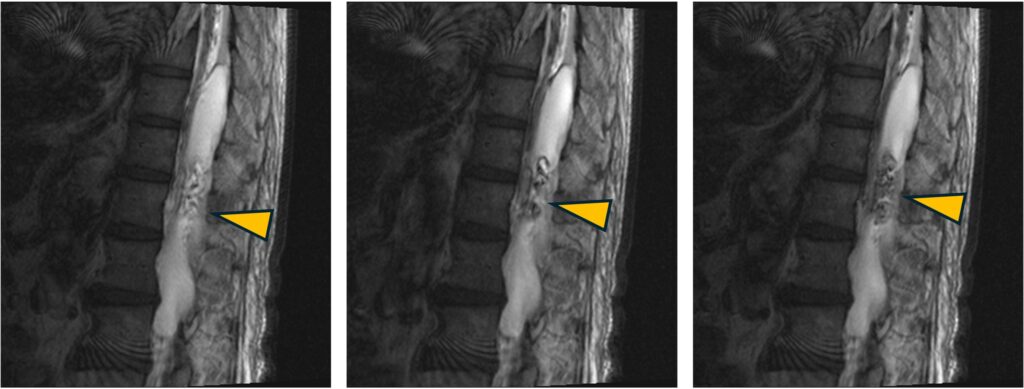

・腰椎クモ膜嚢胞

嚢胞が交通性かどうかを確認する際、PSIF撮像により交通部位がdephaseされ強調されます。